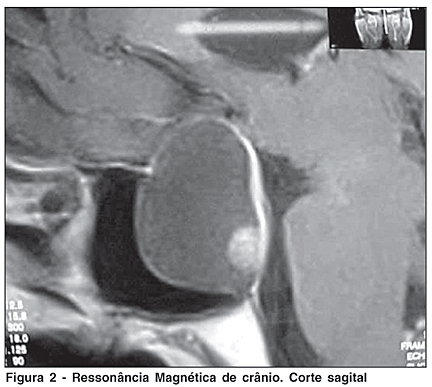

A ressonância magnética evidenciou lesão expansiva cística localizada na sela túrcica, com crescimento supra-selar, medindo cerca de 3,4 x 2,8 cm x 2,4 cm em seus maiores diâmetros, sem realce após o uso endovenoso de contraste. Apresentava obliteração da cisterna supra-selar e importante compressão sobre o quiasma óptico, sugestivo de macroadenoma predominantemente cístico (Figuras 2 e 3).